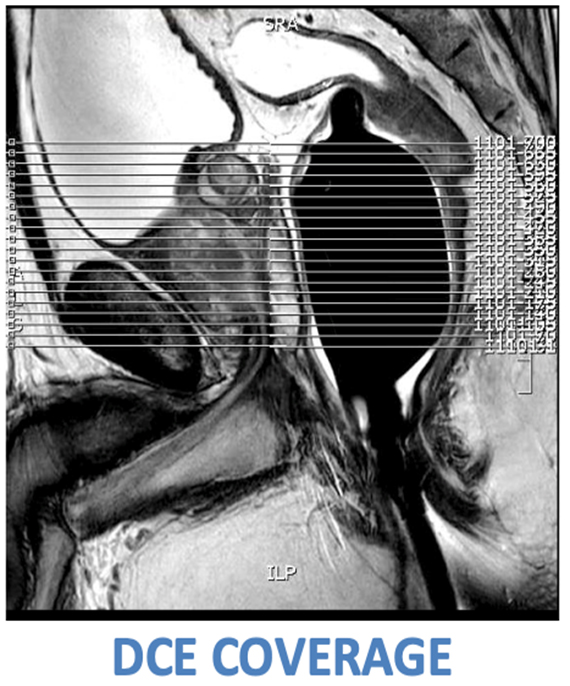

| COR | T2 | TSE | 3mm | 0mm | No | 180x180 | See image for coverage. No need to cover the entire endorectal coil. Only cover prostate and seminal vesicles. |

| AXIAL | DYNAMIC | 3D FFE | OK to increase slices, but ensure the dynamics don't exceed 80 seconds. | 180 x 180 | Cover prostate and seminal vesicles. No post-processing required. Send raw data to PACS and archive. |